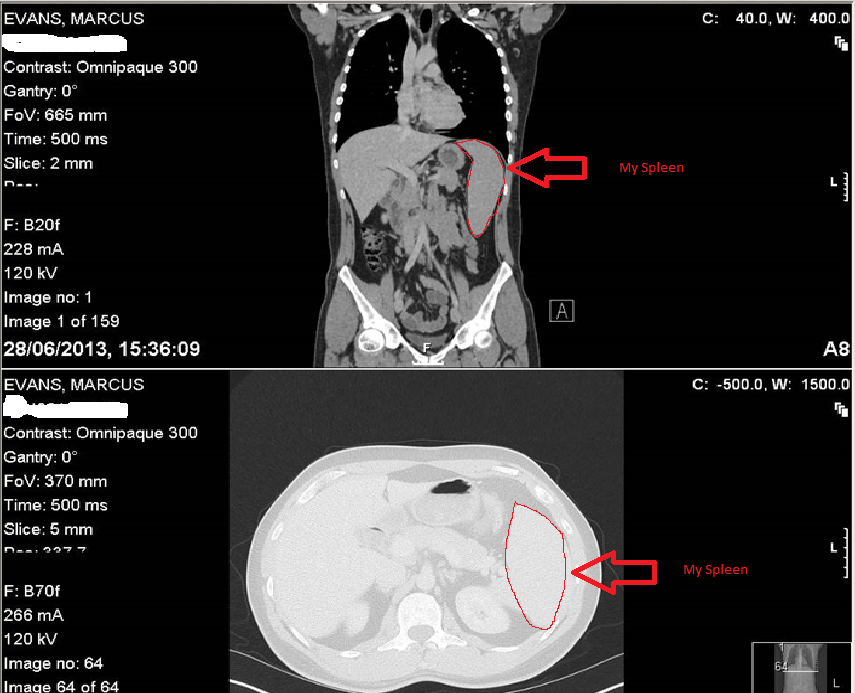

Its a very strange experience seeing your own insides. The Professor showed this to me in a video, the pulsing of my heart and the pumping of my blood. I only have a couple of snap shots to share but yes that is me, at a visceral level. I think we often forget we are all composed of organs, fleshy bits and blood but this brings it home to you. We obviously have consciousness, a mind to think with, an appreciation of art and the abstract but on a very basic level we are just an organic machine. Its important to remember this as machines sometimes go wrong and there often isn’t a reason why. Its not because I inhaled asbestos or ate bad food or bungee jumped, something just went wrong, it just did. Its like your gearbox failing or your clutch slipping. I’m just lucky that what went wrong didn’t write off my machine. These photos are very odd to look at. Welcome to the sum total of my body.

Anyway, I have highlighted my spleen on the picture. I recognise a few of the other organs, feel free to take the picture and mark what they are on there. If anyone does I’ll blog that too.